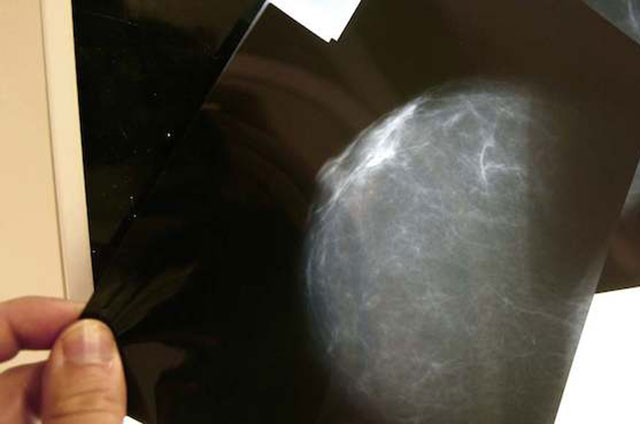

Un grupo de investigadores de Cancer Research UK descubrió un fármaco que puede reducir la expansión del tipo más agresivo de cáncer de mama, según publicó hoy la revista Oncogene.

El compuesto conocido como JQ1 altera la reacción de las células cancerígenas ante la hipoxia o falta de oxígeno, un proceso que se encuentra presente en más del 50 por ciento de los tumores y es más común en los cánceres de mama del tipo triple negativo, el más difícil de tratar.